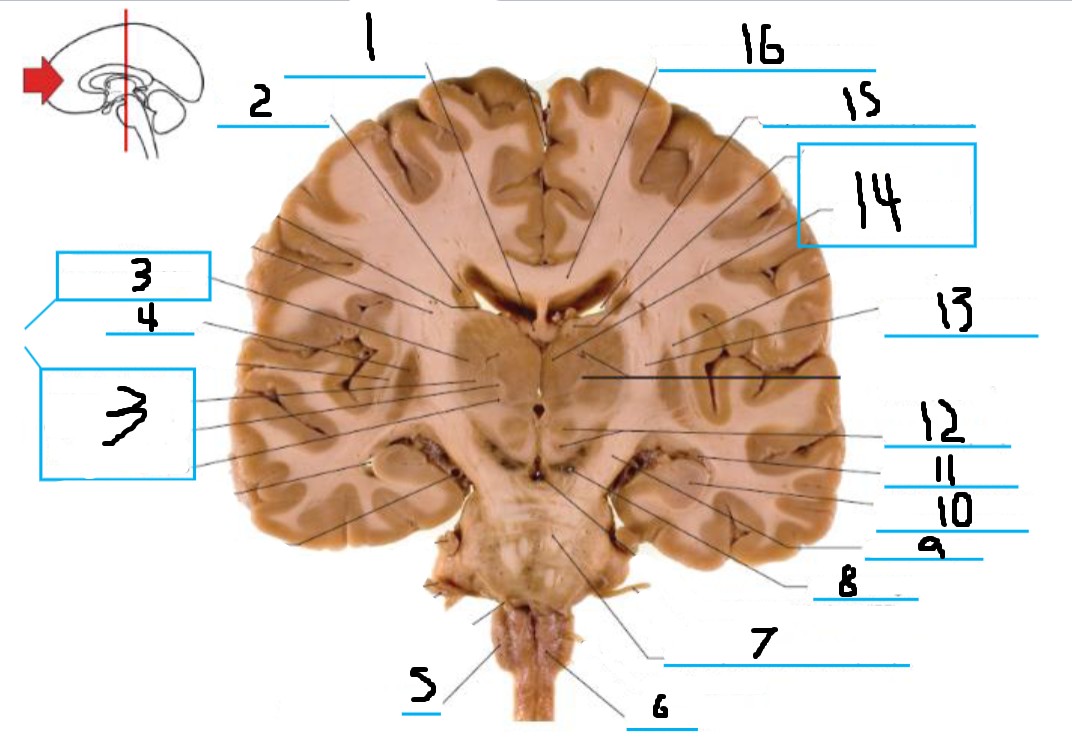

#1 is the:

Corpus Callosum

#2 is the:

Septum Pellucidum

#3 is the:

Lateral Ventricle

#4 and #9 is the:

Globus Pallidus

#5 is the:

Insula

#6 and #8 is the:

Anterior Commissure

#7 is the:

Optic Chiasm

#10 is the:

Putamen

#11 is the:

Internal Capsule

#12 is the:

Caudate